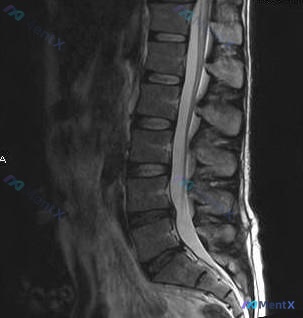

今天分享一例膝关节MRI读片的分析思路,问题是:图像里能发现什么异常,和提问提到的「软骨异常」有什么关系? 病例影像基础信息 这是一张膝关节T1加权矢状位MRI图像,对比度良好,显示膝关节前部结构:髌骨、股骨远端滑车、胫骨近端和髌下脂肪垫,左侧为前侧,右侧为后侧,上为头侧下为足侧。 系统性观察结果...